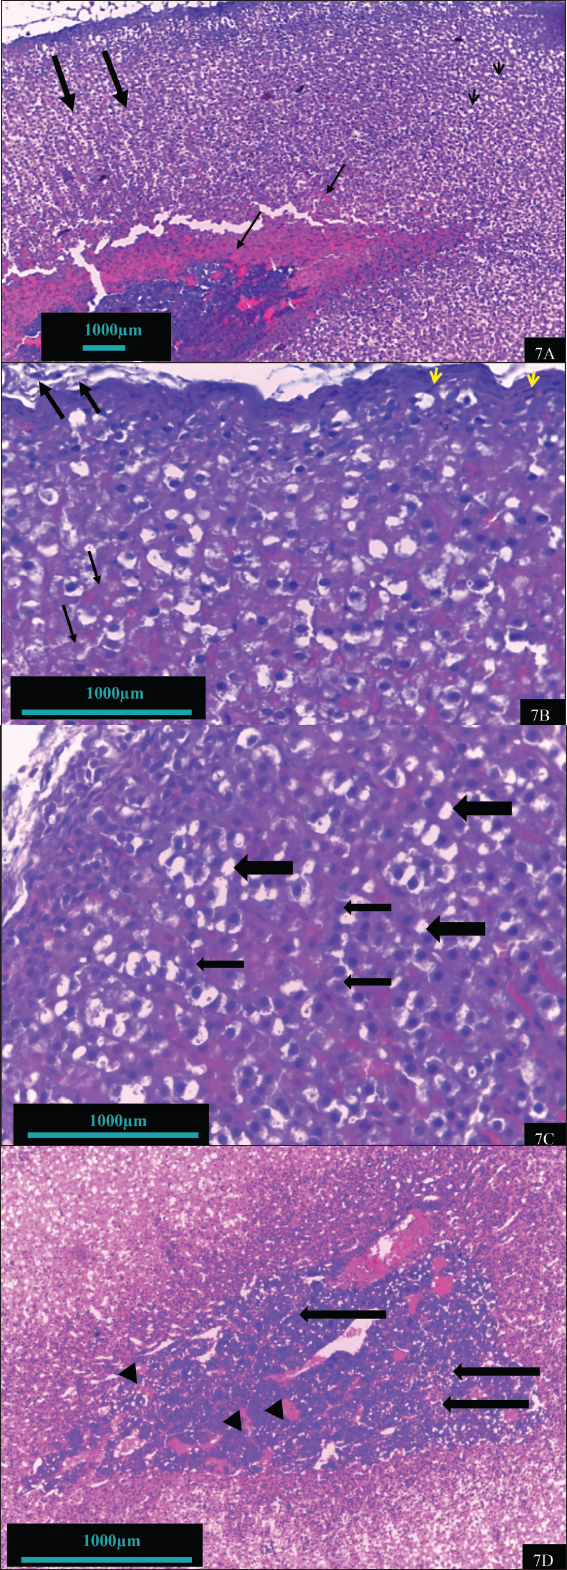

In contrast, the adrenal gland of hypothyroid rats treated with vitamin B12 (hypothyroid + B12) exhibited a notable reparative feature (Fig. 7). Improvements include enhanced capsule integrity, normalization of adrenal cells with clear visible, light-colored nuclei, and restoration of the cellular boundary and cytoplasm. The cell size and number of the cortex and medulla are nearly normal. The features observed in this group are depicted in the control group. The adrenal tissue of rats treated with vitamin B12 exhibited remarkable tissue similarity with the control group (Fig. 8).

Fig. 7. Histomorphohogy of adrenal gland tissues in the hypothyroid rats supplemented with vitamin B12 group showing regular cord-like structures of zona fasciculate (thick arrow), reduced congestion (thin arrow), and slight vacuolations (arrowhead) (7A) (100X). The tissues also showed thick capsule (arrowhead), surrounding adipose tissue (thick arrow), and some nuclei are pale (thin arrow) (7B) (400X). The adrenal cortex showed normal sinusoid (thick arrow) and nucleus (thin arrow) as well as normal cellular architecture (7C); and medulla tissue nearby from normal, chromaffin cell with normal nucleus (thick arrow), as well as slight congestion vascular (arrowhead) (7D).